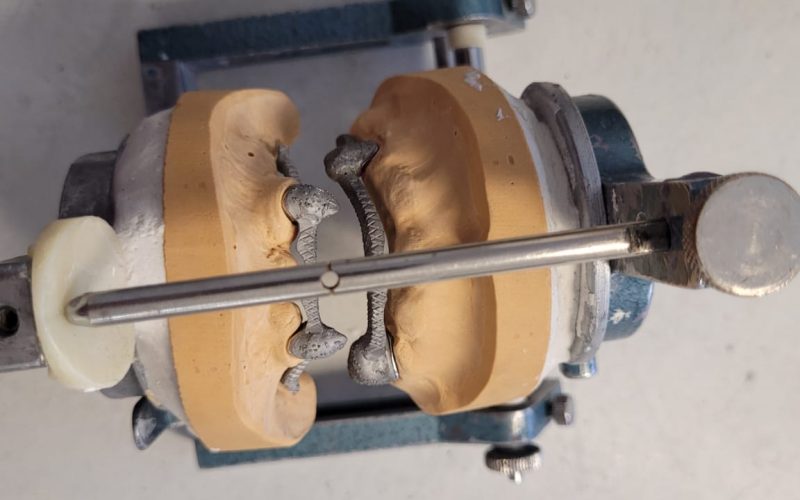

Telescope Crown & Attachment

Our precision-crafted telescope crowns and attachments provide excellent stability and durability, offering an ideal solution for patients requiring a reliable, long-lasting dental restoration.

Gallery

3D Laser Metal Printers for producing strong and intricate metal frameworks with exceptional precision.